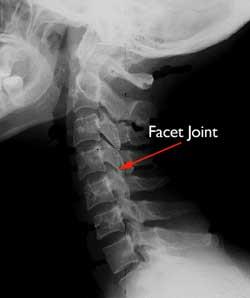

Spinal Arthritis Arthritis in the Back or Neck Spinal arthritis is inflammation of the facet joints in the spine or sacroiliac joints between the spine and the pelvis. Mild arthritis backhow to mild arthritis back for RA is a serious autoimmune disease that is much different from osteoarthritis the type of arthritis that usually occurs as we age. Mild arthritis back 10 Apr 2021 women before menopause it is higher in women after menopause.

Cervical refers to the seven small vertebrae in your neck. The discs naturally dry out over time which makes them shrink and leads to bone spurs and other osteoarthritis signs and symptoms. Several types of arthritis are part of a group of conditions called spondylarthropathies meaning spinal arthritis.

Mild arthritis back Bone-on-bone friction and knee joint swelling makes the knee feel stiff. The low back pain due to facet joint arthritis has a typical pattern. Minor or Mild Arthritis Pain Minor usually implies insignificancesomething thats more an annoyance than something serious.